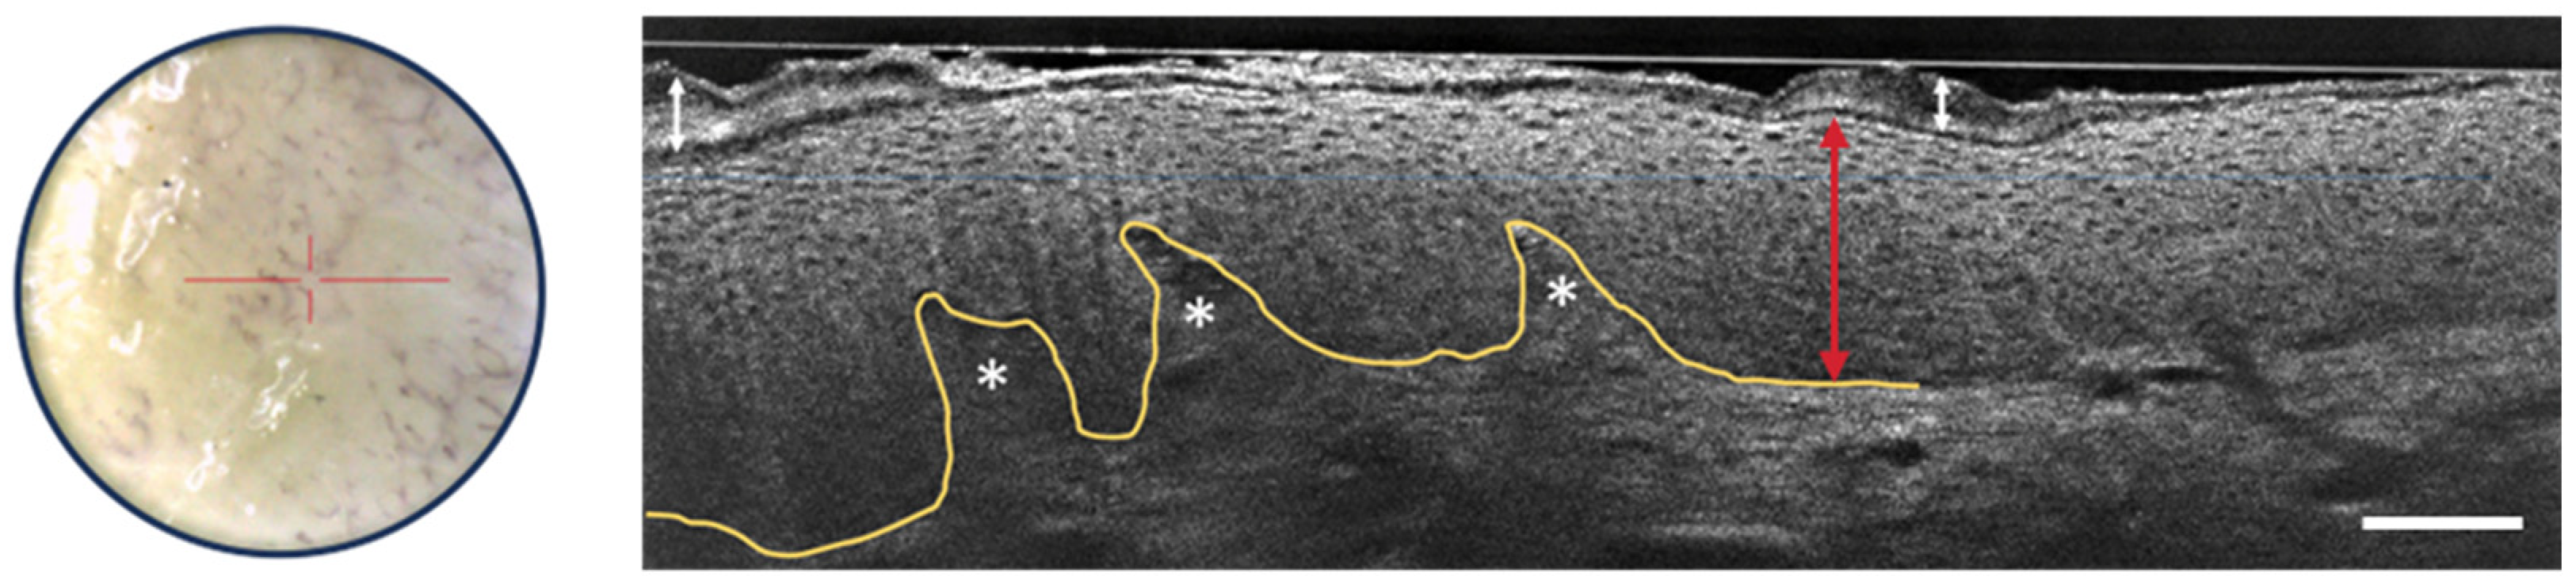

Recent studies and case reports have shown that LC-OCT is a valuable tool for diagnosing various inflammatory and infectious skin conditions, focusing on architectural criteria such as fluid accumulation, changes in epidermal layers, the shape of the DEJ, vascular architecture, the presence of inflammatory infiltrates, and the detection of foreign bodies [49,50,51,52,53]. Figure 10 shows some of the LC-OCT detection criteria of psoriasis. The stratum corneum shows hyperkeratosis. The viable epidermis is also thicker than usual, but the nuclei of keratinocytes are organized regularly. The DEJ is well-defined and undulates due to elongated dermal papillae.

Figure 10.

Dermoscopic image (left) and vertical sectional LC-OCT image (right) of psoriasis. Thickening of the stratum corneum (white arrow with two heads) and of the viable epidermis (red arrow with two heads) with elongated dermal papillae (white asterisks). Keratinocytes nuclei are well organized. Undulated but still well-defined DEJ, which is partially drawn in yellow. The red horizontal line superimposed on the dermoscopic image delineates the location of the vertical sectional LC-OCT image. Scale bar: 100 µm.